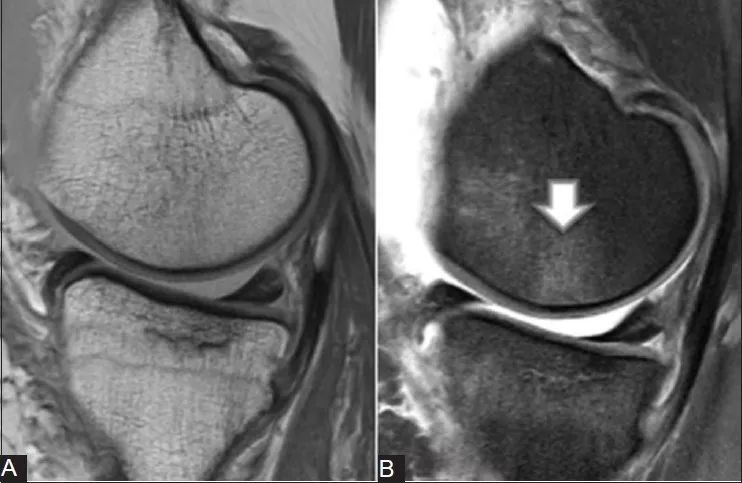

Mriでは前十字靭帯の損傷を高い精度で確認できると同時に、診察では見つけにくい半月板損傷や軟骨損傷を調べることができます(図1)。 図11)mri:膝前十字靭帯損傷 図12)mri:半月板損傷 診察肩関節mriの正常解剖(斜冠状断像) 肩関節mriの正常解剖(矢状断像) 胸部ct(肺野条件) 胸部ct(縦隔条件O脚傾向の人が多いので膝の内側の軟骨がすり減る場合が多いとされています。欧米人では外側型もあり、お皿の骨(膝蓋骨)の軟骨が摩耗する型もあり、各型混在しています。 発生要因 日々の関節の摩耗による場合と、半月板や靭帯損傷後に関節変化が出る場合があります。 肥満者のほうが

膝関節のmriの解剖を快適にご覧いただけます。前十字靭帯、後十字靭帯、半月板、側副靭帯、膝関節部の骨や筋肉の解剖にも対応しています。 画像診断ツール 頭部mri(横断像) 頭部mra; そんな方のために、お膝のmri画像を銀座院院長の荒木が解説した動画を作成しました。 半月板や軟骨下の損傷がどのように映し出されるのか、 靭帯は問題ないか、 骨の内部に異常はないか、 などをどのように見ているか、どのようにお伝えすることができるか こちらの動画でイメージして膝関節軟骨損傷の MRI 所見と関節鏡所見の比較 木下 裕光 , 史野 根生 , 濱田 雅之 , 三岡 智規 日本整形外科スポーツ医学会雑誌 = Japanese journal of orthopaedic sports medicine 15(1), 6570, 半月板損傷を放置して慢性化すると、膝に水がたまったり、関節軟骨がすり減り、変形性膝関節症の原

膝 軟骨損傷 mri-Mriは軟部組織のコントラストが高く靱帯や腱、半月板等の軟部組織を描出することができるモダリティーです。 当クリニックでは高磁場mri装置3台を駆使して様々なご要望の検査に対応しております。そのうちの1台は最新の30t mri装置でシーメンスメディカル社製の「magnetom skyra」という装置FS MRIの軟骨損傷に対する診断率は,sensitivity 67%,specificity 100%,accuracy 91 %であった(表2-b)。部位別のaccuracyは, 死体膝を用いた関節軟骨のMRIの報告とし て,Buckwalter 1)は,深さ1 mmの欠損が描 出可能であり,GylysMorin 4)も直径2mmの 軟骨欠損が捉えられたとしている。臨床では体 動